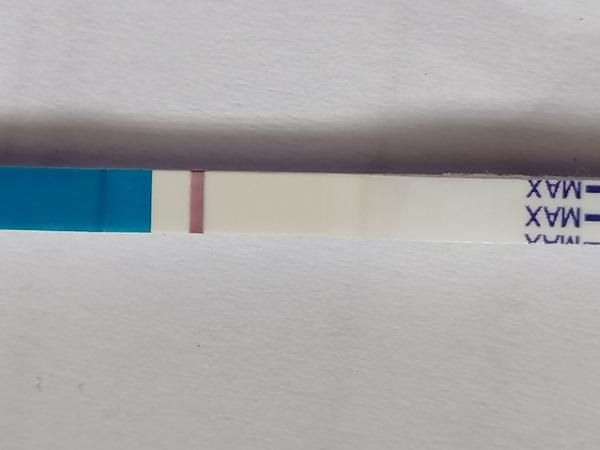

Duch na teste

ahojte babule, mam taku otazku...mate skusenost ze pocas 3 dni vam nesilnela druha ciarka na teste ale bola rovnaka???ako duch????

Ahojte, mali ste aj vy niektorá z vás príznaky skôr ako pozitívny test? Ms by mala prísť v stredu alebo štvrtok, nemám to vždy presne.. A dnes ráno som si robila test a je biely, nič tam nevidím.. Od štvrtka mi je zle na žalúdku, nechutenstvo do jedla občas mám taký ako keby tlak dole, a štvrtok som aj zvracala.. A nahovárať si to nenahovaram lebo aj ráno vstanem a už len pijem vodu lebo myslím ze sa zas po vraciam.. 👶🤔 Neviem čo to je skúsim ešte v štvrtok spraviť test ak sa MS nedostaví, lebo teraz tam nič nevidím